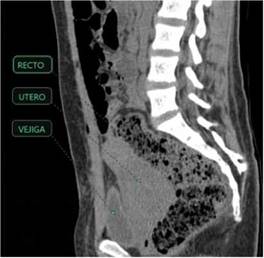

Figura 5: Tomografía de abdomen simple corte sagital con malformación Mulleriana tipo 4. Utero didelfo de aspecto irregular aumentado de tamaño con obstrucción hipodenso de la cavidad uterina y canal vaginal.(hematómetra y hematocolpos)